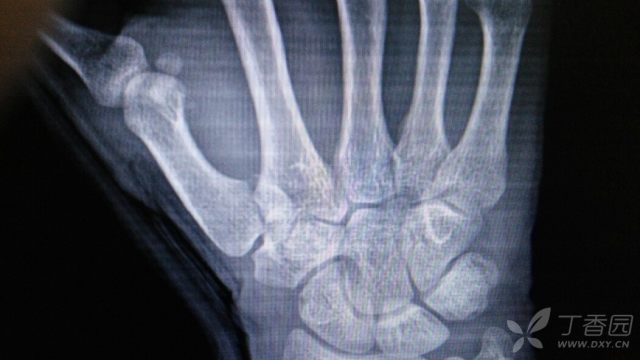

第一掌骨基地部骨折!

640x360 - 28KB - JPEG